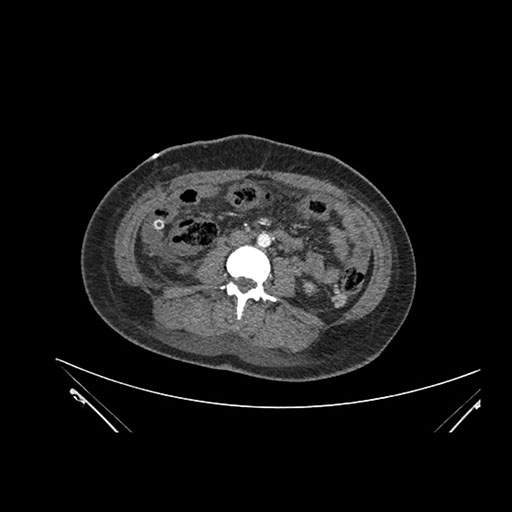

Imaging Analysis

Look through the patient's CT scan to identify any areas of concern for the necessary procedure.

Coronal Arterial

Based on initial findings, which issue(s) would you be most concerned about?